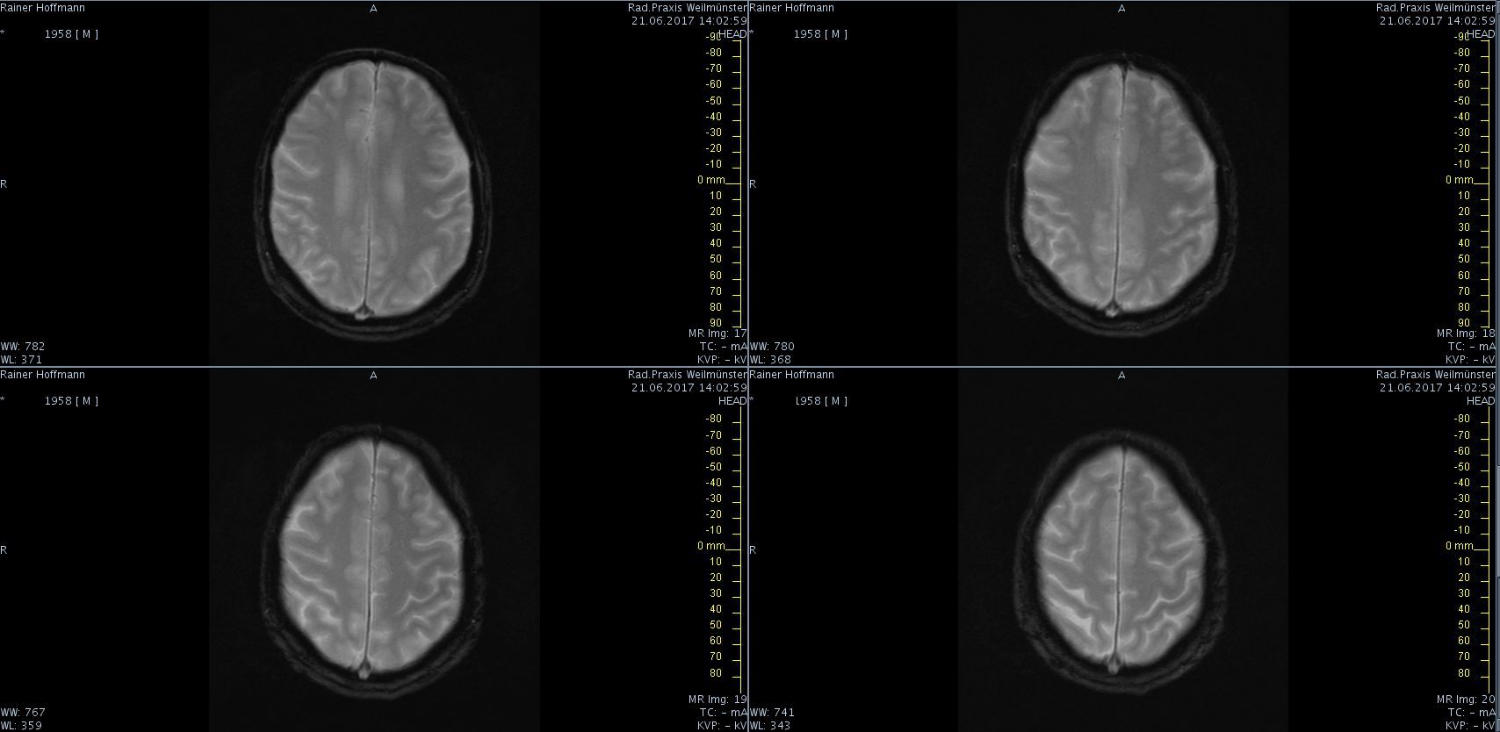

Das ist ja ganz toll, dass Ihr die Seite so schnell gefunden habt. Ich zeige euch jetzt ein ganz, ganz anderes Paßfoto von mir. Es könnte Ähnlichkeiten zu anderen lebenden oder bereits verstorbenen Personen geben. Wenn Ihr das erste Bild oben links anklickt wird es ver- größert dargestellt. Dann kann man mit den Pfeiltasten am unteren Bild- rand durch meinen Kopf blättern. Es gibt nicht viel zu sehen. Vielen Dank an Martina für Ihre Hilfe.

MRT